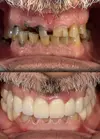

Zirconium Applications

Implant Treatment

Porcelain Applications